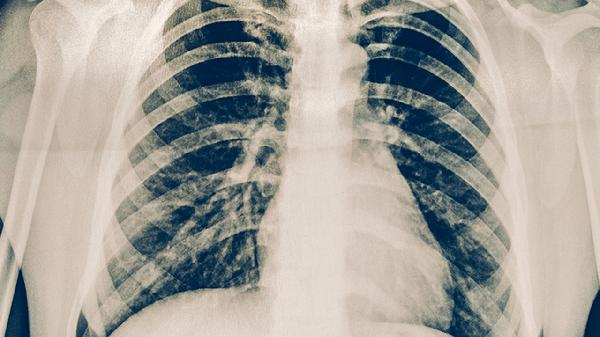

典型病變包括滲出性炎癥、增生性結(jié)核結(jié)節(jié)和干酪樣壞死。肺部可形成空洞病灶,愈合時(shí)出現(xiàn)纖維化和鈣化。血行播散會(huì)導(dǎo)致粟粒性肺結(jié)核,支氣管播散可引起肺內(nèi)病灶擴(kuò)散。

痰涂片抗酸染色是基礎(chǔ)檢查,結(jié)核菌素試驗(yàn)適用于篩查。胸部X線(xiàn)可見(jiàn)上葉尖后段浸潤(rùn)影,CT能發(fā)現(xiàn)早期微小病灶。GeneXpert核酸檢測(cè)可快速確診,痰培養(yǎng)仍是金標(biāo)準(zhǔn)但需時(shí)較長(zhǎng)。